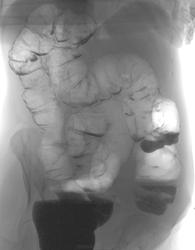

Женщина средних лет. Клинически - колит с однократным стулом в виде мясных помоев. Колоноскопия - 120 см, явных образований не выявлено, слева слизистая кровит при контакте с эндоскопом.

Ирригоскопия назначена для уточнения состояния правой половины толстой кишки (эндоскоп "не достает")

Вашему вниманию представлены два фрагмента исследования, что скажете? Каковы варианты обьяснения подобной картины?

Не нравится мне восходящая кишка.

Проксимальная треть поперечки - скорее сфинктер. А дистальная треть восходящей - нет полной картины, хочется еще картинок. Пока думается на сдавление извне, но подрытость нижне-наружного контура дефекта возбуждает, и очень.

Напрягает стойкое циркулярное сужение в восходящем отделе . Вряд ли это сфинктер.Отмечается на обоих снимках.В остальных отделах - измечивость деформаций контура..

Хотелось бы увидеть буквы. Как бы не оказалось неполным поворотом кишки. Плохо не видеть глазом. Кажется слепая кишка распложена слева.

Есть долихосигма и сужение в восходящей кишке.

Скопически этого сужения НЕ БЫЛО...как и на прицельном снимке за экраном.

Это сжиматель (сфинктер) Гирша.

Со сфинктером согласна, но ещё цепляет неровность верхнего контура в селезёночном изгибе на обоих снимках.

Что касается случая , имхо: органической патологии не определяется.

Трудно сказать...меня "не впечатлило"...но 100% исключить ЧТО ТО в СТЕНКЕ, естественно, не могу))))